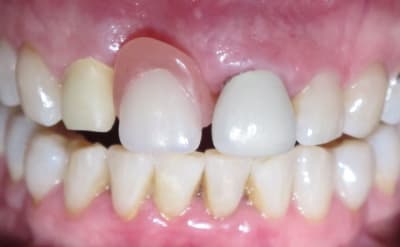

Pas emballé. L'esthétique est certes sympathique, mais il sera absolument impossible pour le patient d'assurer une hygiène correcte là-dessous. Paro à prévoir de manière rapide...

Cas d'implant pour moi (et quand je dis pour moi, c'est pour mon correspondant).

Si vraiment on se tourne vers le bridge, pourquoi pas élongation coronaire 21, ce qui aurait permis de fermer le diastème de manière plus conventionnelle...

Pour mon correspondant, impossible de faire un implant.

Pas de CCM car après une longue discussion avec le prothésiste, cela nous a paru être la solution la plus esthétique dans ce cas (diastèmes importants)